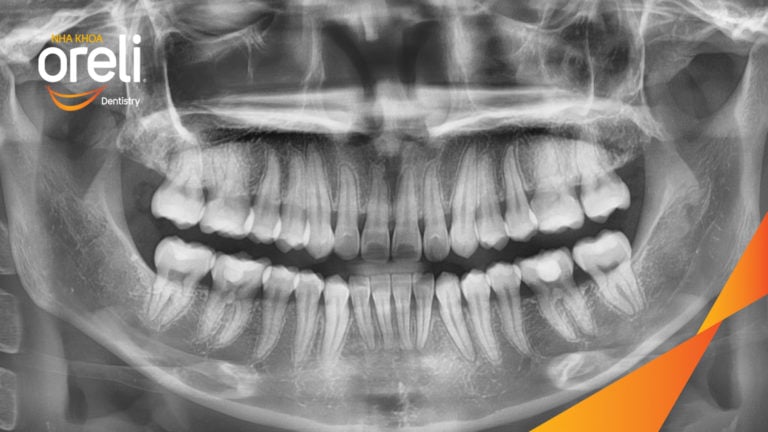

Ca niềng chỉnh chen chúc hẹp hàm nặng cả trên và dưới – Kết quả điều trị thực tế tại nha khoa Oreli Niềng răngChen chúc Xem thêm